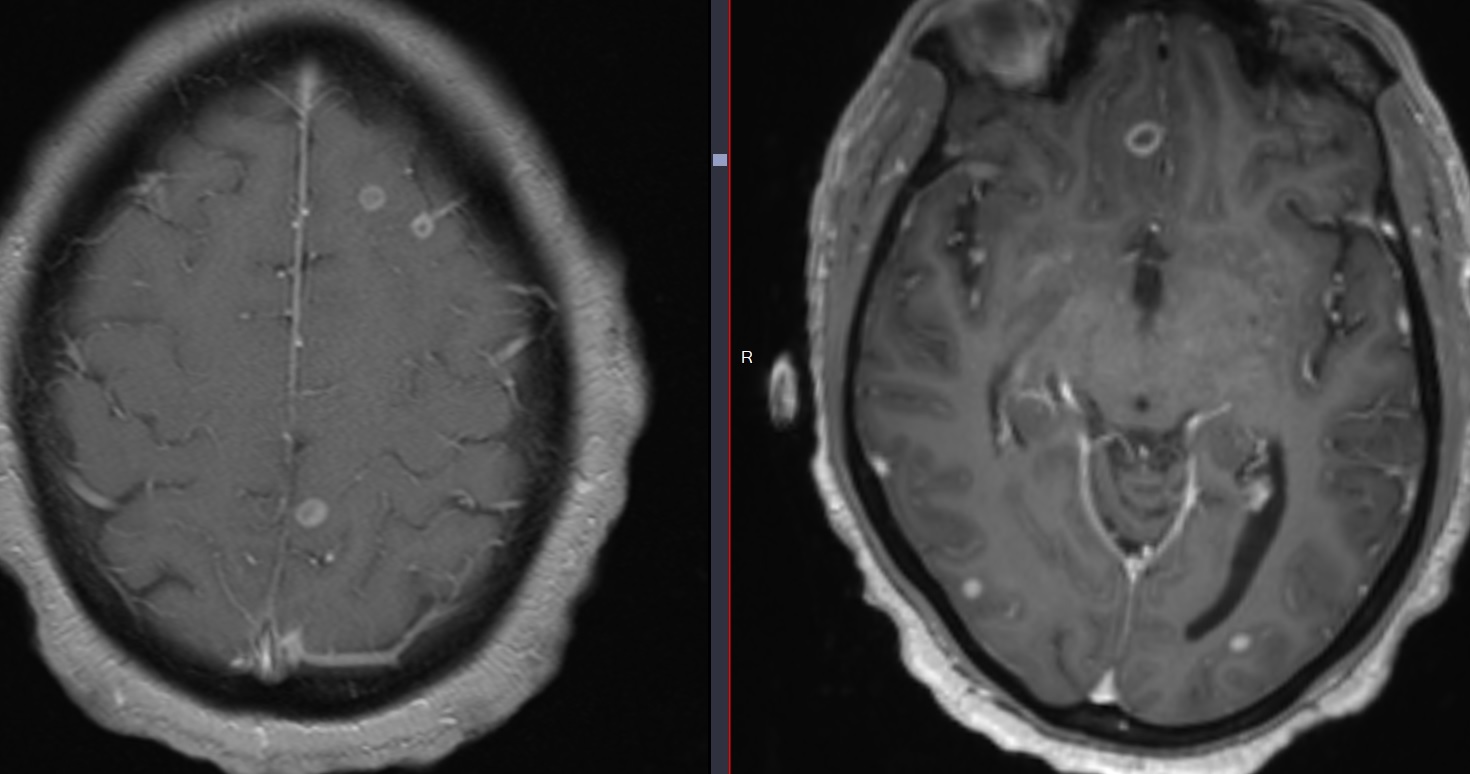

• Leptoméningite tuberculeuse (prise de contraste leptoméningée)

• Tuberculomes (abcès avec centre hypoT2)

Tuberculomes